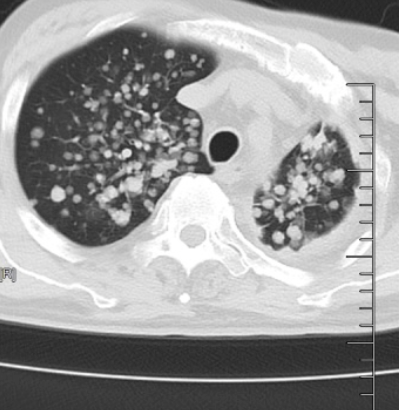

IVB期肺腺癌转移,脑内布满密密麻麻转移瘤!北大人民青岛医院肿瘤科帮七旬老人绝地求生!

近期,70岁的李先生(化名)在家人的搀扶下,步履蹒跚地来到北京大学人民医院青岛医院肿瘤科找到庄兴俊主任。